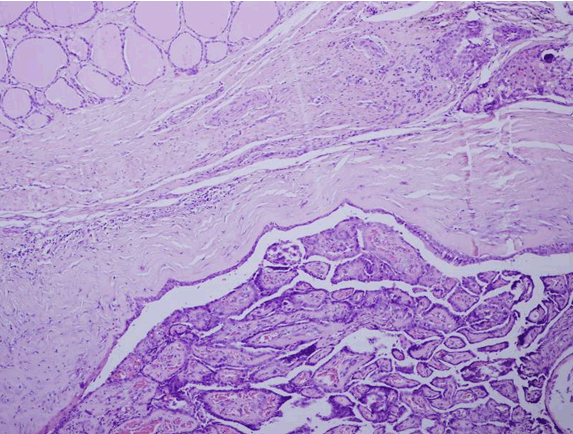

Microscopic examination revealed a cyst lined by respiratory and squamous epithelium. Its lumen revealed a papillary carcinoma, composed of complex, branching randomly oriented papillae with fibrovascular cores and many psammoma bodies. The wall of cyst revealed islands of normal colloid-filled thyroid tissue as well as foci of papillary carcinoma (Figure 2) and (Figure 3). The papillae were lined by cuboidal cells with optically clear and overlapping nuclei, some showing intra-nuclear inclusions and nuclear grooves (Figure 4). The tumor measured 1.1 cm. Connective tissue surrounding the cyst showed many lymphoid aggregates and fibrosis. The tumor was very close to one resection margin. The hyoid bone did not show any tumor.

Figure 2: Thyroglossal cyst lined by respiratory epithelium with papillary carcinoma inside its lumen. Wall shows normal thyroid follicles (upper left corner). Small focus of papillary carcinoma with psammoma bodies also seen (upper right corner), (H&E stain, x100).

Figure 3: Thyroglossal cyst with papillary carcinoma in its wall (H&E stain, x100).